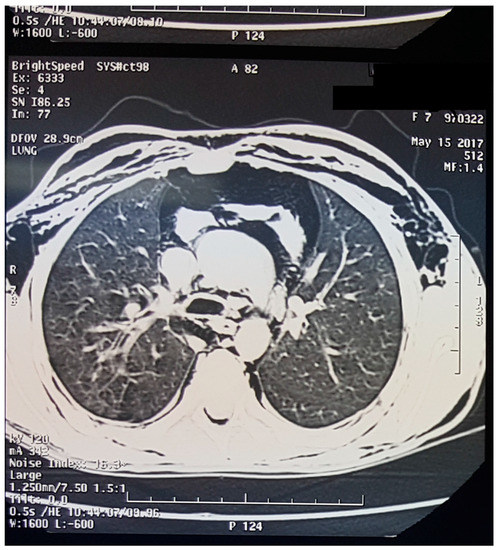

A Case of Spontaneous Pneumomediastinum with Subcutaneous Emphysema in Children

2. Case Presentation